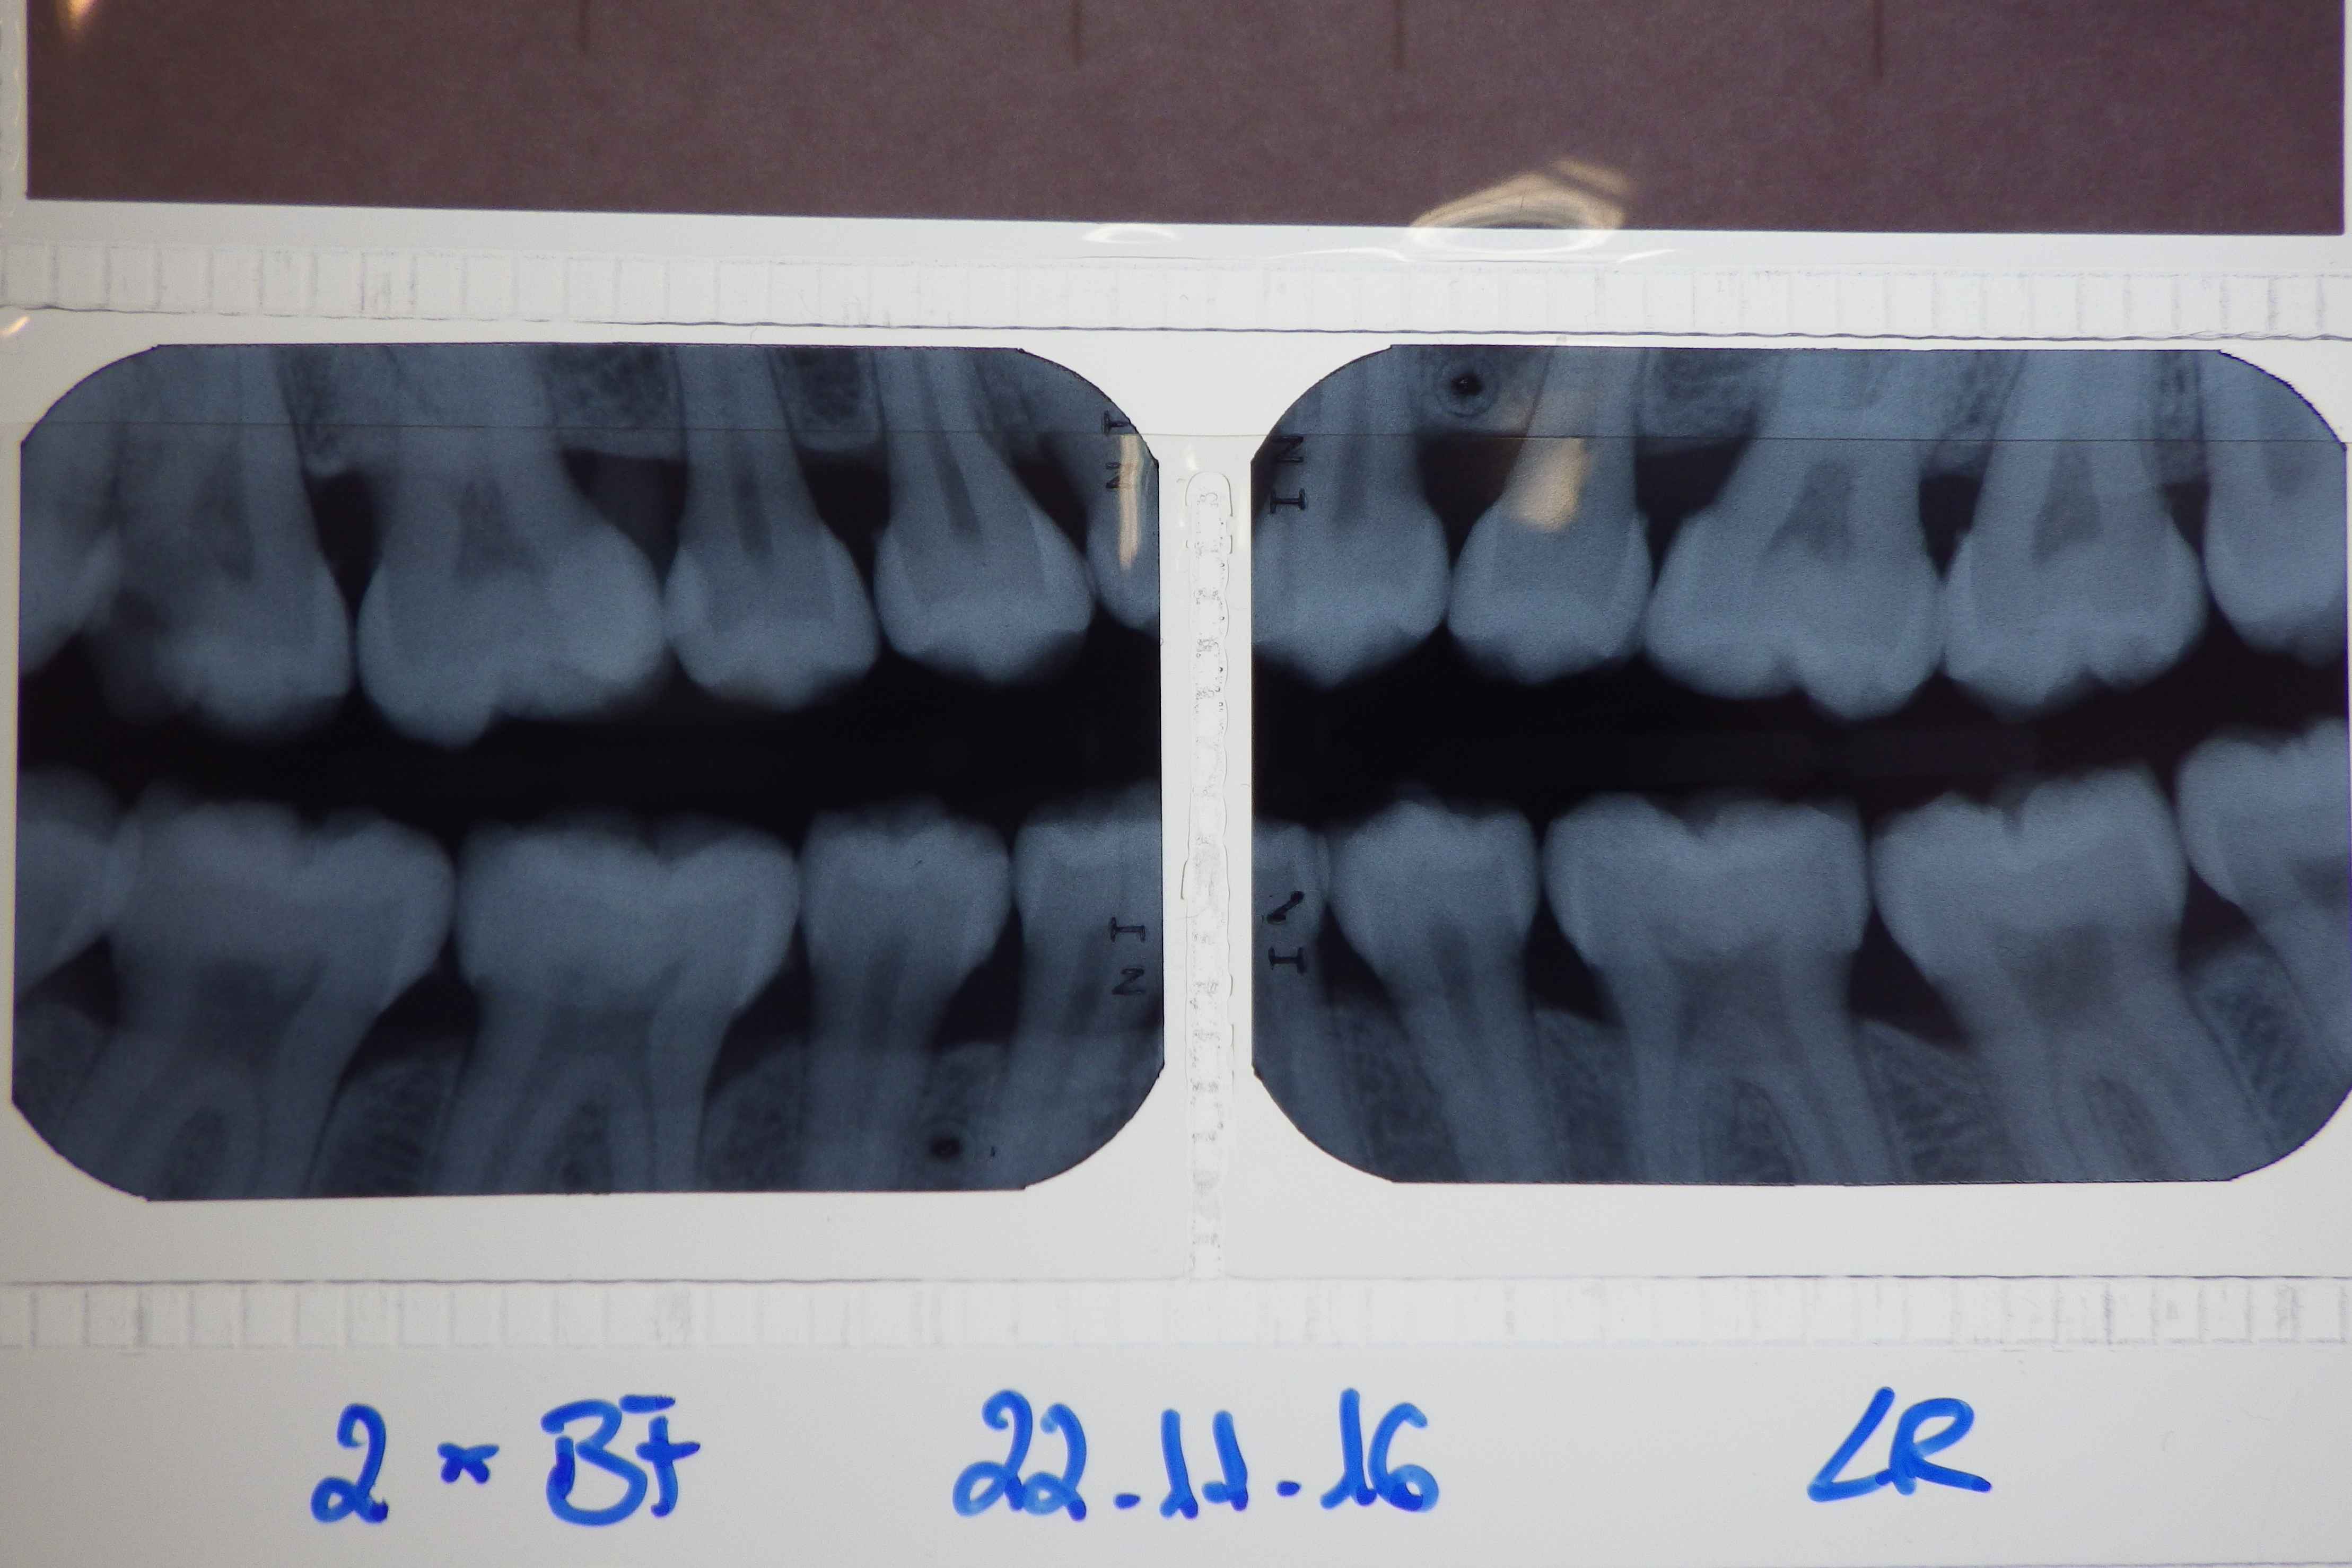

g-bissfluegel-roentgenaufnahmen Veröffentlicht 6. Januar 2017 am 4435 × 2957 in Neupatientin mit Sammlung seltener Befunde